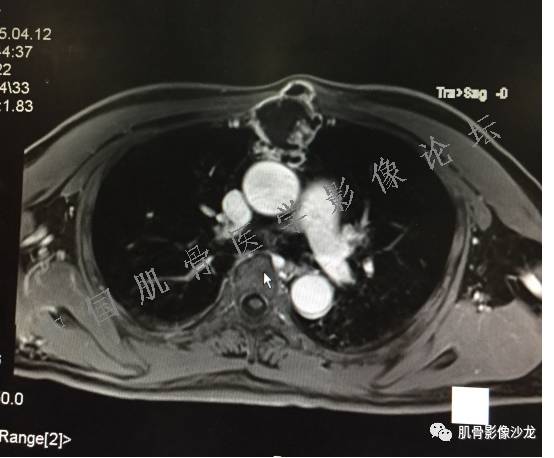

1、软骨肉瘤可以有膨胀性骨质破坏(病例3,4),可以有溶骨性骨质破坏(病例2),局部皮质因为破坏变薄,中断 ;

2、软骨基质T2WI高信号,软骨小叶分叶状,也就会出现高老师提到的骨内膜扇贝形压迹。一般认为骨内膜扇贝形压迹超过骨皮质厚度的2/3是软骨肉瘤在长管状骨的特征性表现。如上图。3、软组织肿块或肿胀;

4、 钙化,环形,弓形,边缘模糊 ;

5、增强后进行性延迟,不均匀分割状强化, 会强化的纤维间隔,软骨小叶不会强化,关于老师们说到的钙化,软骨肉瘤不一定会有钙化 。